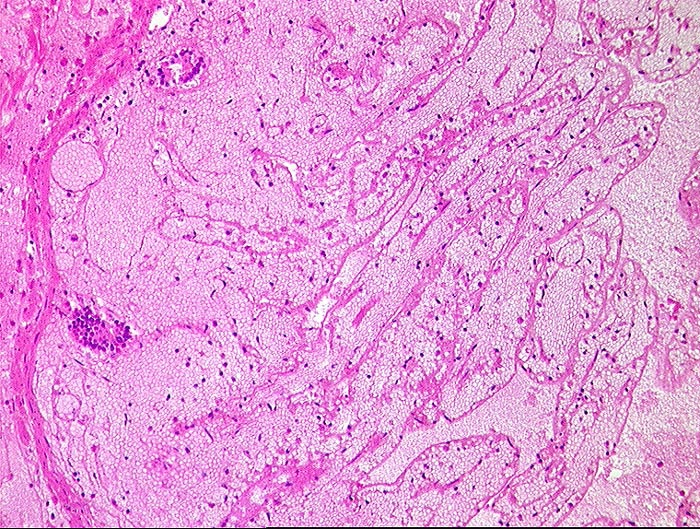

PathoPic ID 432 - embolischer Mesenterialinfarkt

embolischer Mesenterialinfarkt

vaskulär / Durchblutungsstörung

Dünndarm

Hämorrhagische Nekrose der Mukosa.

Alter Myokardinfarkt Parietalthrombus. Frische Emboli in eröffneten Ästen der Arteria mesenterica superior.

Histologie